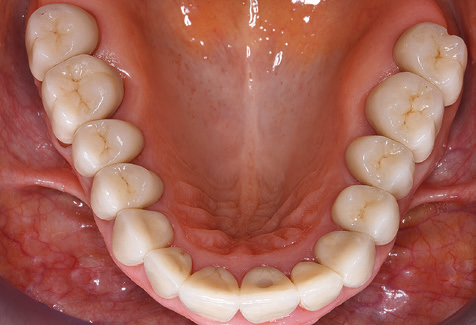

Due to the presence of periodontal disease, SPT was performed every three months in the first years following the insertion. The patient demonstrated a high degree of motivation and good compliance. The pocket depths recorded annually revealed a stable periodontal situation with a BOP index of below five per cent. On the basis of the stable periodontal situation and good cooperation on the patient’s part, the recall interval was extended to every six months as of the sixth year of the prosthetic function phase. Following the change in the recall interval, the respective annual documentation of the periodontal status continued to reveal a stable periodontal situation with no increase in the pocket depths and a BOP index below five per cent (Fig. 2a and b).

The ten-year check-up revealed no indications of advancing clinical attachment loss or peri-implant bone substance loss (Fig. 3).